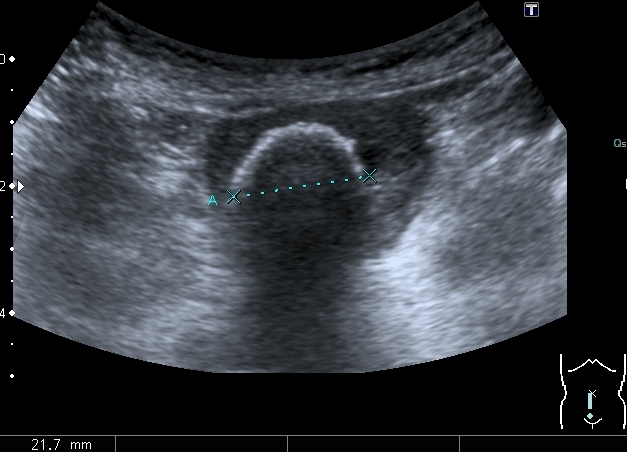

Ребёнок 4-х лет с терминальной гидроцефалией (объём мозгового черепа около 6 - ти литров на глаз), тетрапарезом, вторичным сколиозом 4-й степени, двухсторонним вывихом тазобедренных суставов, глуьокой умственной отсталостью поступил в детское хирургическое отделение. Мать отмечает в течение последних 2-х месяцев кровянистые выделения на памперсе, в последние несолько недель беспокойство ребёнка. В анализе мочи - гематурия.

Произведено УЗИ с бльшими техническими трудностями из - за сопутствующей ортопедической и неврологической патологии

Сокращённый мочевой пузырь

Он же в поперечном скане

Нейрогенный мочевой пузырь (?), МКБ, конкремент мочевого пузыря, двухсторонний мегауретер, конкремент правой почки.

Если честно, и я изначально не совсем понял, где находится конкремент (а это конечно же конкремент), локализованный на урограммах. При первичном исследовании на УЗИ его я не видел (либо он спрятался за тенью конкремента мочевого пузыря, либо я обрадовался редкой находке конкремента такого размера в мочевом пузыре - 2.5 см, и не посмотрел что ниже). Тем не менее при ретроспективном анализе архивированных сонограмм, как мне кажется, он попал в один из сканов, м.б. не совсем чётко.

I20111114160229796.jpg

И всё -же, где конкремент :?: